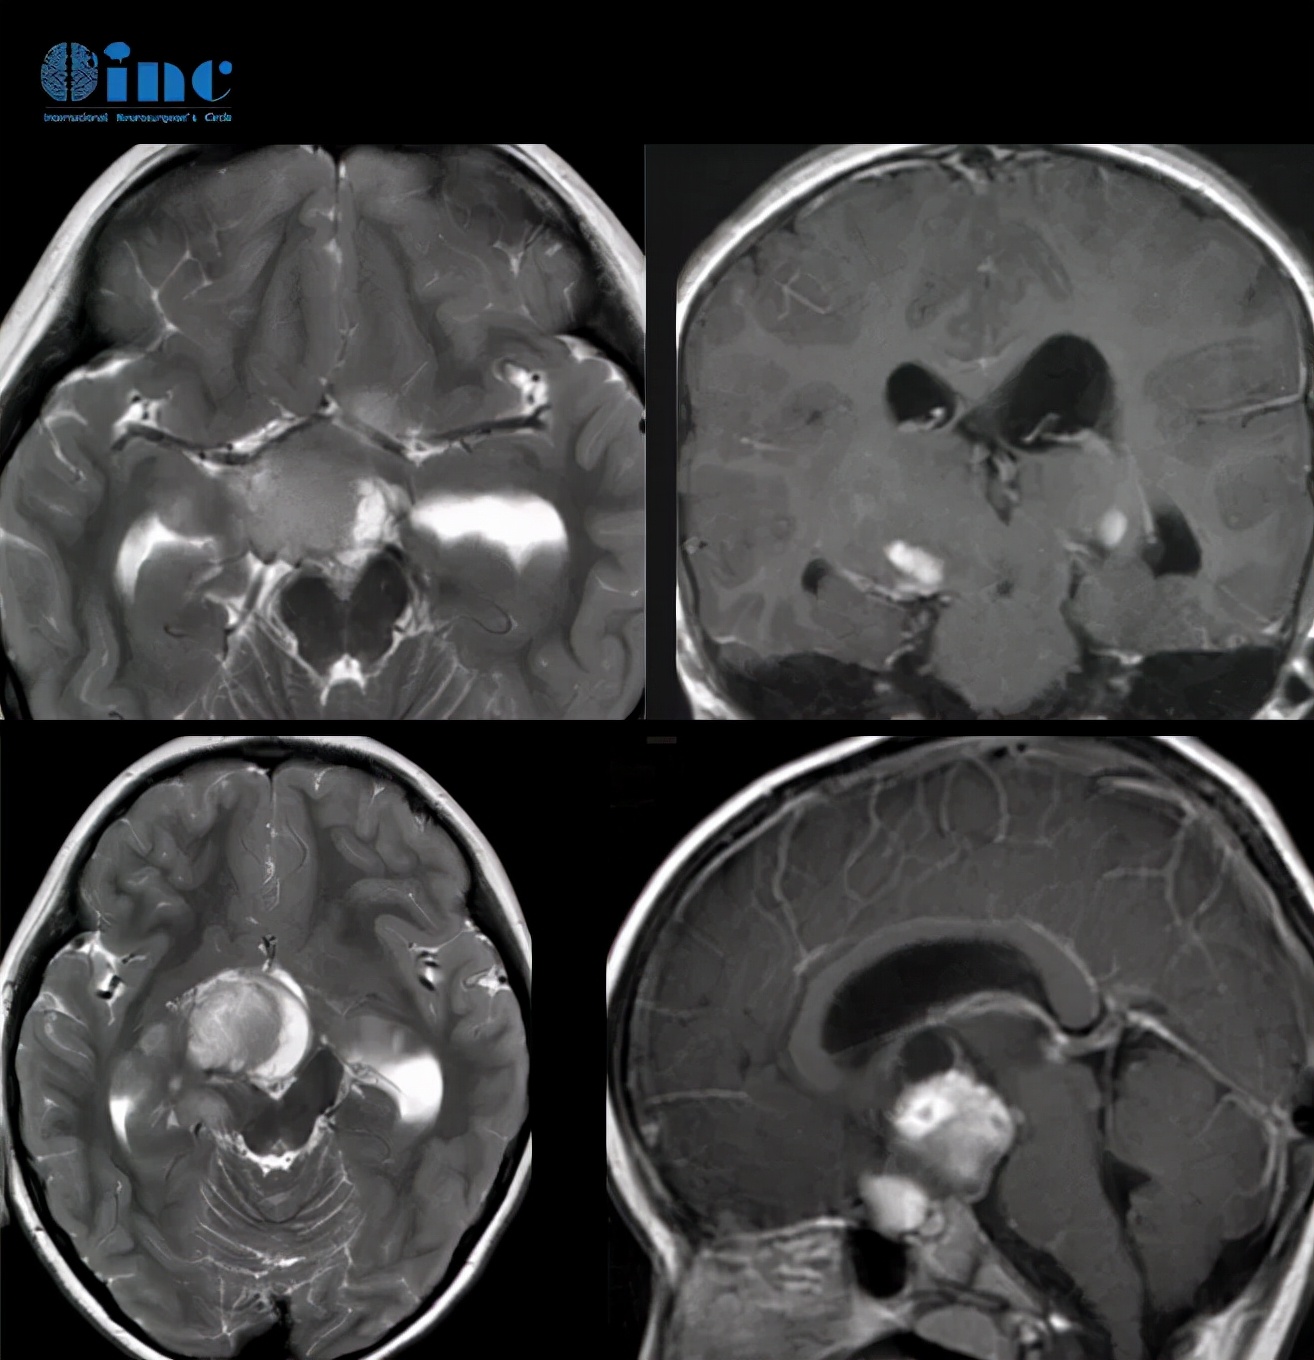

康康的术前MR影像

术前情况:康康因视力下降、头痛、呕吐就医发现“右侧基底节区及下方占位、鞍区占位”,因肿瘤引起的脑积水也日益加重,故在国内儿童医院先进行了脑室腹腔分流术。

由于肿瘤涉及的解剖结构,如视神经,视交叉,视束,视放射、丘脑底垂体轴、边缘系统、第三脑室、脑底动脉环等,康康出现了视力下降、头痛、呕吐等症状,随之而来的可能还有内分泌引起生长发育异常、认知发育缓慢和心理、行为功能障碍,第三脑室的肿块产生阻塞性脑积水等……

1、关于肿瘤性质和最佳治疗方案,INC巴特朗菲教授指出:显然,这是一个双侧视神经系统下丘脑胶质瘤,并在两个视束内延伸,从增强冠状位MRI切片可以看出。为尽可能地保全原有视力、最快解除巨大占位效应,最合适、有效的治疗方法是手术切除,两侧视束内延伸至丘脑后方的肿瘤部分无法通过手术正常切除,将继续留在原地。这些肿瘤部位以后必须进行化疗,1-2年后再进行放疗。